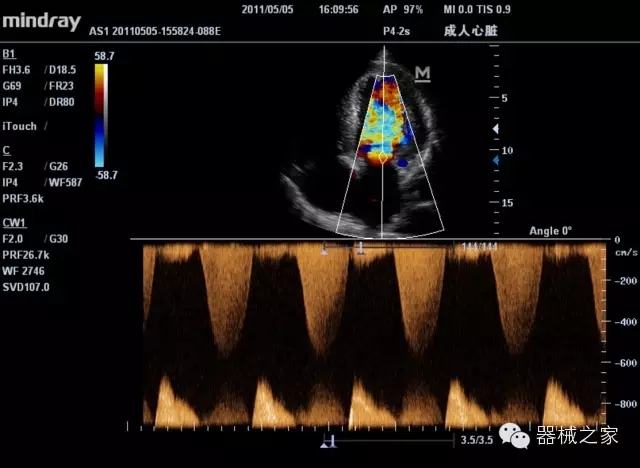

經(jīng)典產(chǎn)品:M7(星鉆)

臨床圖片賞析

產(chǎn)品特點(diǎn)

·裝載有采用Multi-Core多核處理的非嵌入式平臺(tái),成像效率大大提高,并且能夠給用戶帶來高速、多任務(wù)并行信號(hào)處理體驗(yàn);

·優(yōu)秀的圖像效果、強(qiáng)大的功能體驗(yàn)、豐富的探頭選擇、合理的便攜式設(shè)計(jì),全中文顯示及病人管理界面,使得M7在任何場(chǎng)合、任何時(shí)候都能快速響應(yīng)更好的心血管、腹部、婦產(chǎn)、小器官等常規(guī)超聲檢查以及肌骨、神經(jīng)、顱腦、術(shù)中等新興領(lǐng)域的使用需求;

8倍波束并行處理系統(tǒng)

·在便攜式緊湊平臺(tái)上采用更多倍波束并行接收信號(hào)處理模式,無(wú)論二維還是彩色血流圖像狀態(tài)下,擁有更靈敏的回波頻移捕獲能力,大大提高時(shí)間分辨率,尤其使得心血管表現(xiàn)更為突出;